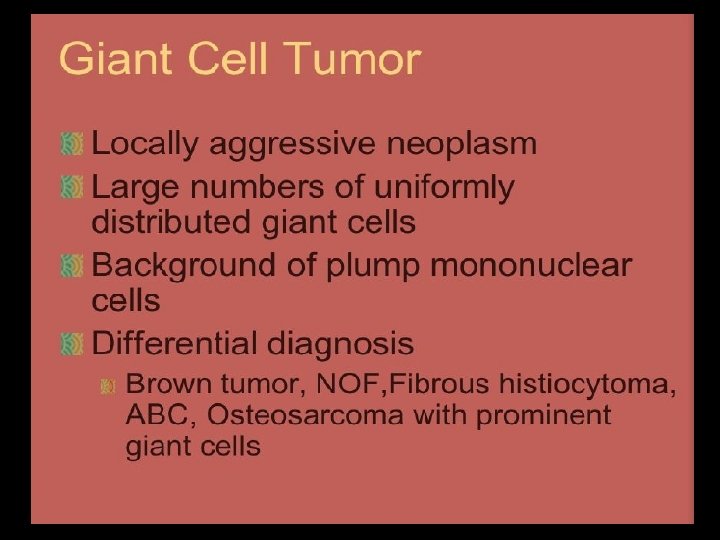

Giant cell tumour • • Uncertain origin Occurs in mature bone Area of old epiphysis Distal femur, proximal tibia, proximal humerus, distal radius.

TREATMENT OPTIONS 1. Curettage & bone graft 2. Curettage & bone cement 3. Excision without replacement 4. Excision & replacement with: Artificial prosthesis (custom made) Allograft 5. Excision & replacement with upper end fibula 6. Excision & arthrodesis